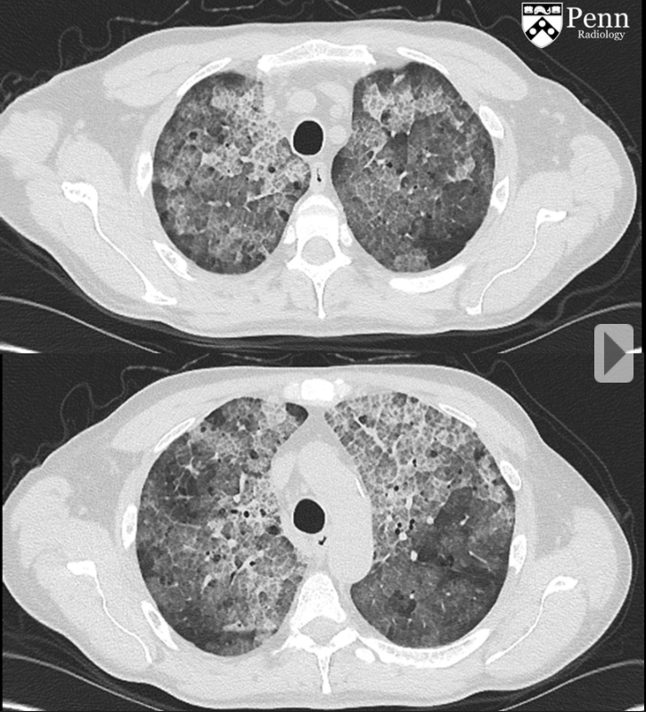

Pulmonary alveolar proteinosis

ground glass plus crazy paving

treatment = bronchoalveolar lavage

middle aged woman with chronic mild SOB. No smoking history